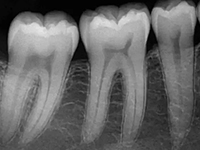

深圳博愛曙光口腔專家表示:採取補牙術是為了阻止齲齒繼續惡化。所謂補牙就是採用用人造物質修補牙體缺損的方法,用於修補的物質叫充填材料。凡因齲齒、楔狀缺損、外傷等造成牙體組織缺損者都需要修補,以恢復其外形和功能。

全面口腔检查,并根据龋齿的数量、疗位、龋病的病变程度制定最佳的补牙修复方案。

除净病变组织,保护牙髓和健康牙齿组织,建立良好的固位形和抗形,以免造成继发龋。

早龋,一次消毒即可进行补牙,中龋或深龋,则需m三至五次,如果涉及到牙神经则需根管治疗。